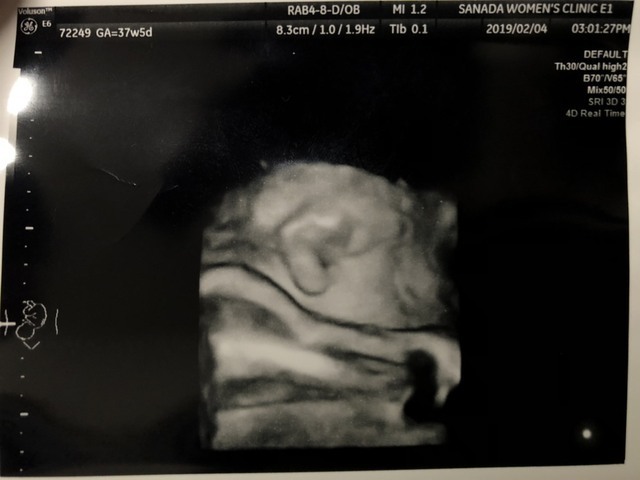

37週1日(37w1d・男の子)|あっこ☆さん さん(39歳)

エコー写真撮影時のエピソード:

過去に子宮筋腫の手術歴があったため、陣痛が来てはいけないと、38週で帝王切開を予定していました。

添付は入院前、最後の検診で撮ったエコー写真です。

なんとか手術まで待って欲しい…

と願っていましたが、検診の3日後に破水して緊急手術となりました。

コワイと感じる間も無かったので良かったかもしれません(笑)